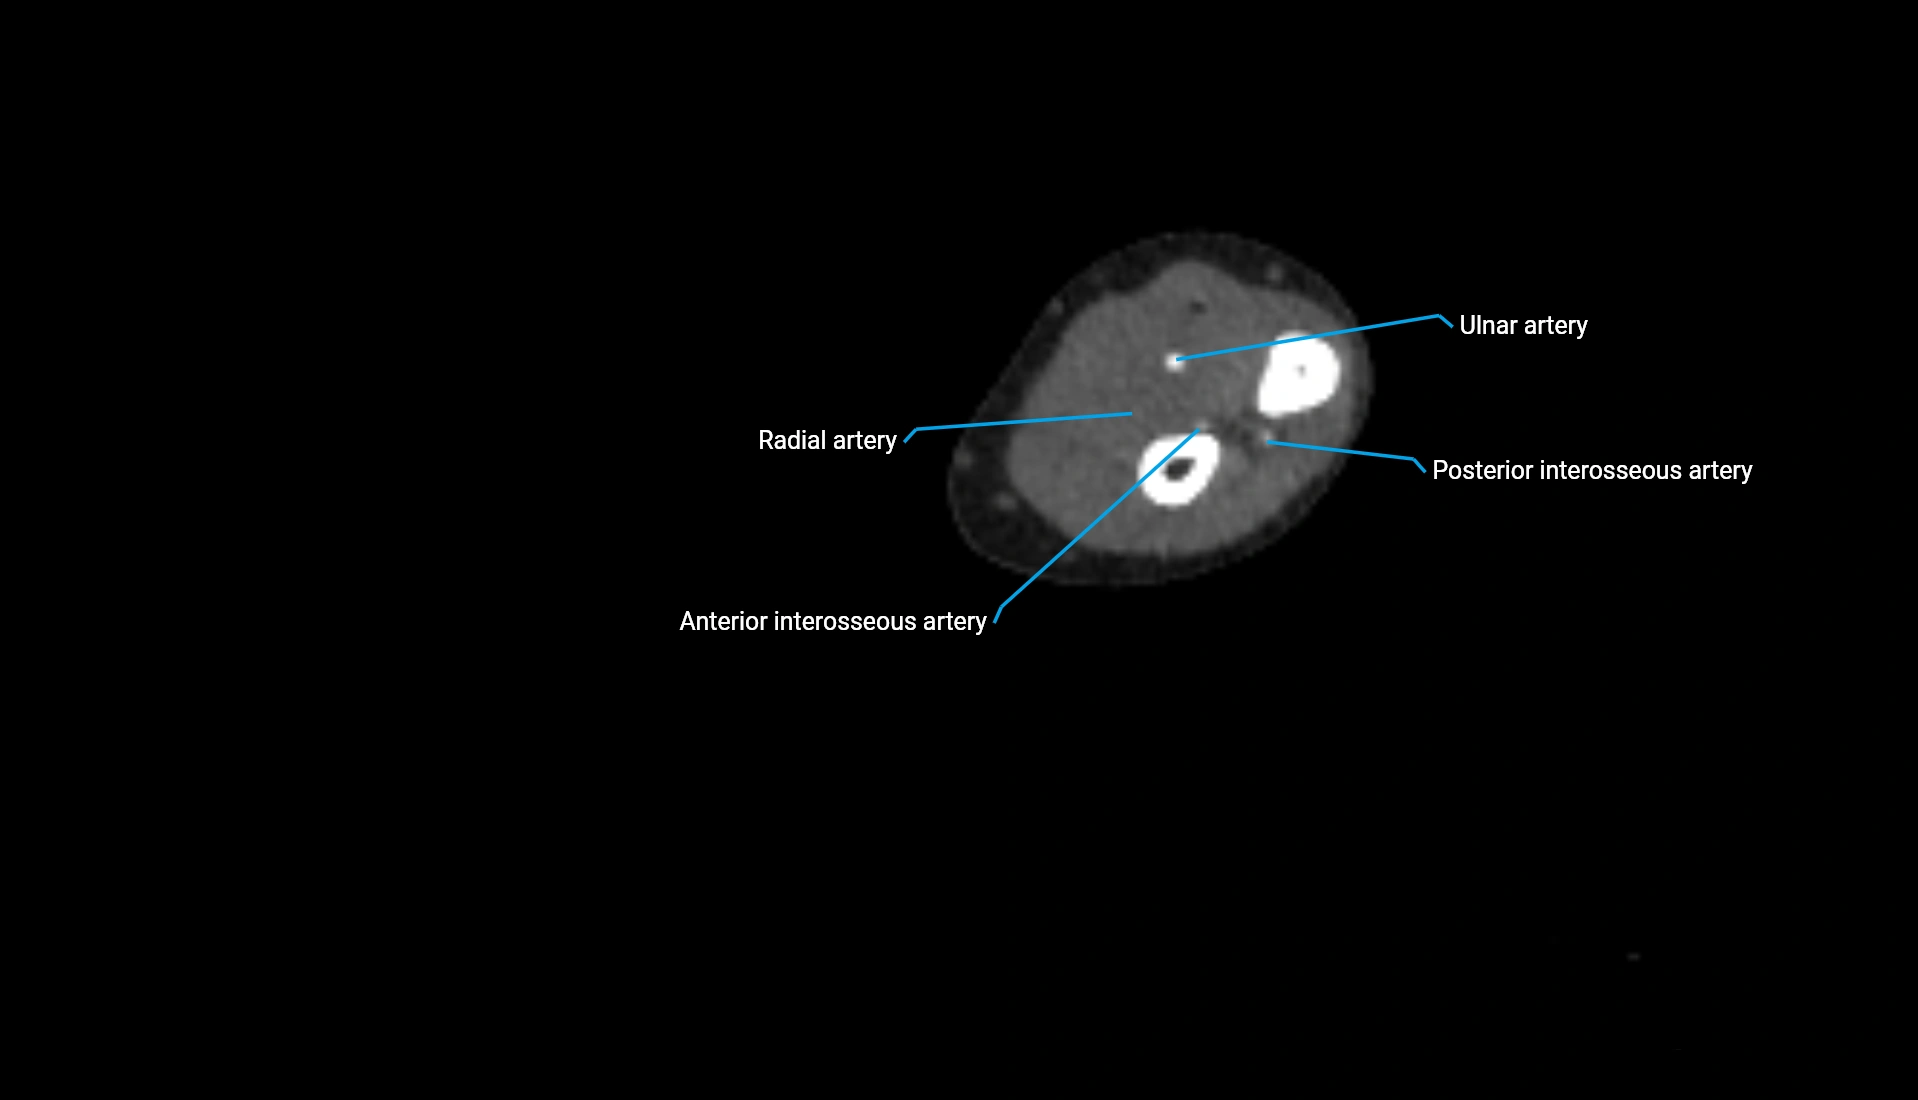

CT Appearance

Non-Contrast CT:

• Cortex: High-density, sharply defined

• Subchondral bone: Dense cancellous matrix

• Articular surface: Smooth concave contour articulating with the capitellum

• Excellent for evaluating bone integrity, alignment, and subtle fractures